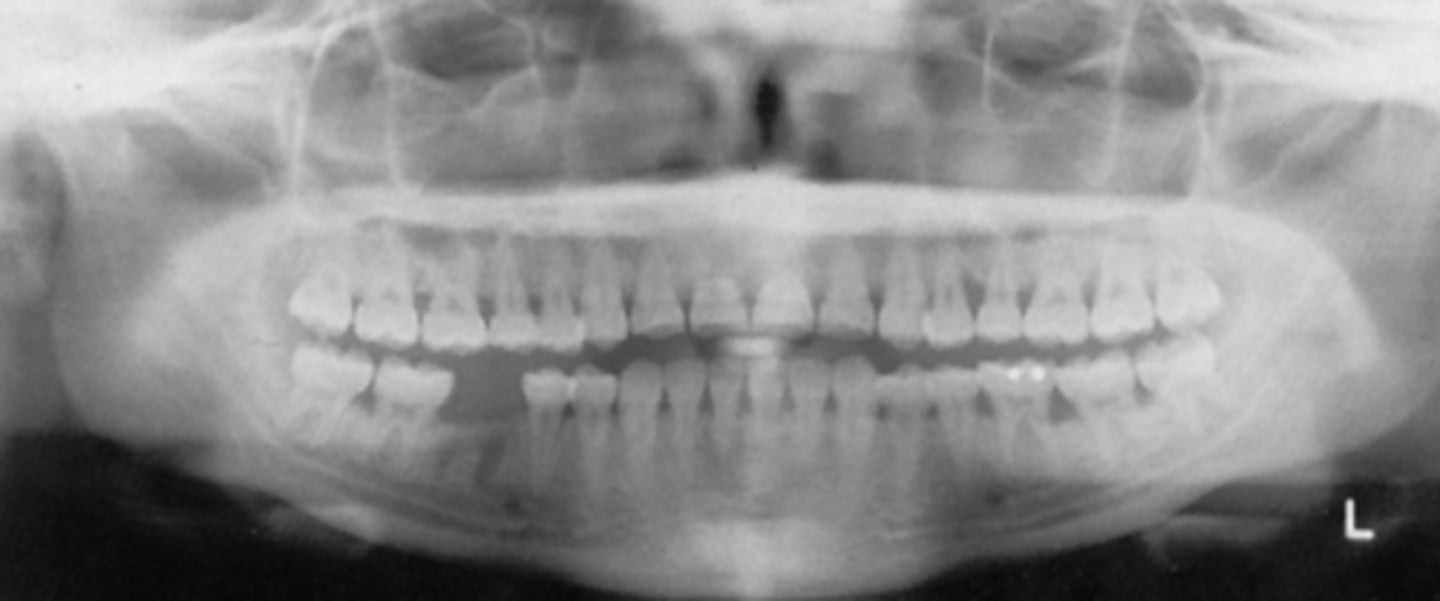

patient is too close to sensor

What is the problem with the patient's positioning in this image?

C) focal trough

What light would need to be adjusted to fix this image?

A) mid-sagittal

B) Frankfort plane

- patient didn't close all the way

- chin was down

- patient is too close to the film/receptor

What are the problems in this panoramic image?

What light needs to repositioned to fix this image?

What light needs to be repositioned to fix this image?